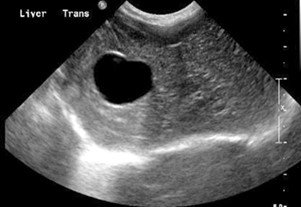

Kedi Köpek Ultrason / Kedi Köpek Kalp Ultrasonu / Kedi Köpek Ekokardiyografi / Kedi Köpek Gebelik Ultrasonu , evcil hayvanınızın iç yapılarından yansıyan yüksek frekanslı ses dalgaları yayınlayarak çalışır. Cilde tutulan küçük bir prob, en yaygın olarak mide, böbrekler, karaciğer, dalak ve safra kesesi gibi karın organlarını incelemek için kullanılan iç vücudun bir görüntüsünü oluşturmak için geri dönen sinyalleri toplar. Bir ekokardiyografi ( eko ) veya kalbin ultrasonu, kalp kapakçıkları, kan akışı, odacık boyutu ve kasılmalar hakkında kesin bilgi sağlar. Bu araç, genel kalp sağlığını değerlendirirken ve kardiyovasküler hastalığı tedavi ederken çok önemlidir. Ultrason radyasyon gerektirmediğinden, evcil hayvanlarda gebelikleri ve cenin sağlığını izlemek için de jinekolojik amaçlı kullanılır.

Ultrasonografi, radyografiler (x-ışınları) gibi diğer teşhis araçlarıyla birlikte kullanıldığında, kardiyovasküler hastalık, iskelet kırıkları, bazı kanser türleri, yumuşak doku hasarı, yabancı cisimler ve organ hastalıkları dahil olmak üzere çok çeşitli anormallikleri saptayabilir. Tamamen ağrısız ve invaziv olmayan ultrasonlar, veterinerlik endüstrisindeki en hassas teşhis araçları arasında yer alır.